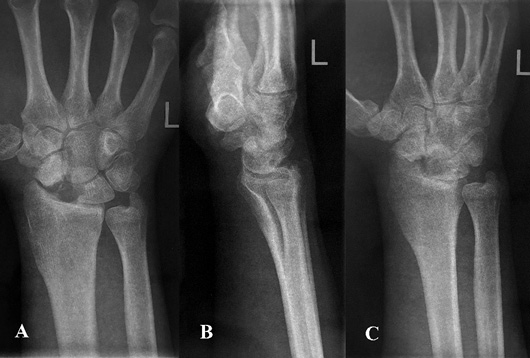

2 pav. Kairiojo riešo trijų krypčių rentgenogramos po operacijos: priekinė rentgenograma (A), šoninė rentgenograma (B), įstrižinė rentgenograma (C)

Operacijos metu atliktas pjūvis kairiosios plaštakos nugariniame paviršiuje tarp trečiojo ir ketvirtojo tiesiamųjų sausgyslių kompartmento laivelio projekcijoje. Naudojant bukąją ir aštriąją disekciją, pasluoksniui pasiektas kaulas. Rastas nesugijęs laivelio lūžis. Pašalintos proksimalinio laivelio segmento lūžgalių skeveldros, distalinė laivelio dalis rezekuota iki gyvų audinių. Vėliau atliktas apie 5 cm ilgio skersinis pjūvis ties VI dešiniojo šonkaulio krūtinkauliniu galu (mokslinėje literatūroje aprašoma atvejų, kai rekonstrukcijai naudojami V–IX šonkaulių osteochondriniai fragmentai [22, 24, 25]). Naudojant bukąją disekciją, pasluoksniui pasiektas ir nuo aplinkinių audinių, antkaulio ir krūtinplėvės atpreparuotas šonkaulis, atlikta dalinė jo rezekcija. Paimtas apie 3 cm kaulinės ir kremzlinės šonkaulio dalies fragmentas, kuris toliau formuotas pagal laivelio kaulinio defekto formą. Atsižvelgta į rekomendacijas, kad, formuojant transplantatą, jam fiksuoti ir funkcio­nuoti būtina palikti bent 2–3 mm storio šonkaulio kaulinio audinio ir 5 mm šonkaulio hialininės kremzlės [22, 24]. Autotransplantatas perkeltas į proksimalinį laivelio galą, fiksuotas dviem Kiršnerio vielų atkarpomis (žr. 2 pav.). Pjūviai pasluoksniui užsiūti, kairioji plaštaka imobilizuota gipso longete 3 mėn.

Pacientas pakartotinai klinikoje apsilankė praėjus 6 mėn. po rekonstrukcinės operacijos. Jis buvo patenkintas klinikiniais operacijos rezultatais, nes be apribojimų galėjo grįžti prie kasdienių veiklų ir darbo. Atlikus plaštakos goniometriją (žr. 3 pav.), įvertinti klinikiniai rezultatai, pasitelkiant modifikuotą Greeno ir O’Brieno riešo funkcijos balą ir Quick Disabilities of the Arm, Shoulder and Hand (QuickDASH) klausimyną, taip pat atliktos riešo rentgenogramos. Modifikuotas Greeno ir O’Brieno riešo funkcijos balas siekė 95. Balo įvertis, palyginti su pradiniu, prieš rekonstrukcinę operaciją apskaičiuotu įverčiu, padidėjo daugiau negu 20 balų, visų vertintų kategorijų, išskyrus riešo judesių amplitudę, įvertinimai buvo aukščiausi, atitinkantys sveikosios plaštakos rodiklius. Įvertinus Quick Disabilities of the Arm, Shoulder and Hand (QuickDASH) klausimyną, apskaičiuota skaitinė išraiška siekė 4,55 balų, t. y., palyginti su pradiniu įverčiu, sumažėjo 9,09 balų. Paciento atsakymuose fiksuoti minimalūs kasdienės veiklos ribojimai. Taip pat atliktos kairiojo riešo trijų krypčių rentgenogramos (žr. 4 pav.).

triju.jpg

4 pav. Kairiojo riešo trijų krypčių rentgenogramos, praėjus 6 mėn. po operacijos: priekinė rentgenograma (A), šoninė rentgenograma (B), įstrižinė rentgenograma (C)